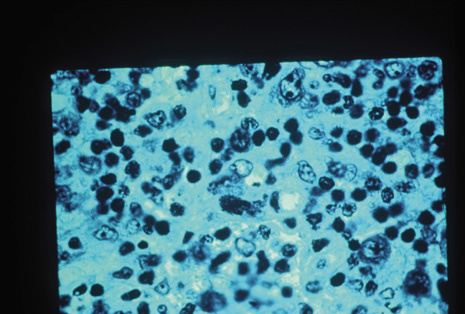

Many forms of uveitis are characterized by specific types of inflammatory cells. Usually, however, one encounters mixtures of cell types in any given specimen, with the relative percentages of lymphocytes and polymorphonuclear leukocytes varying. There may be unusual numbers of eosinophils, or macrophages laden with lens material may be present. Thus, an enumeration of the cells and a careful analysis of their structure can be useful as a diagnostic aid (Figs. 7, 8, 9, 10, 11, 12, 13, 14, 15, 16, 17, 18, 19, and 20). Figure 15 demonstrates eosinophils that were aspirated from the anterior chamber of a patient with Toxocara canis endophthalmitis. Figure 12 demonstrates malignant cell infiltrate from the vitreous, showing the stained presence of monoclonal light chains being elaborated in the cytoplasm. Interleukin-10, detectable in the vitreous of intraocular lymphoma patients, is also directly indicative of both the clinical activity and the number of malignant cells as observed by cytopathology.